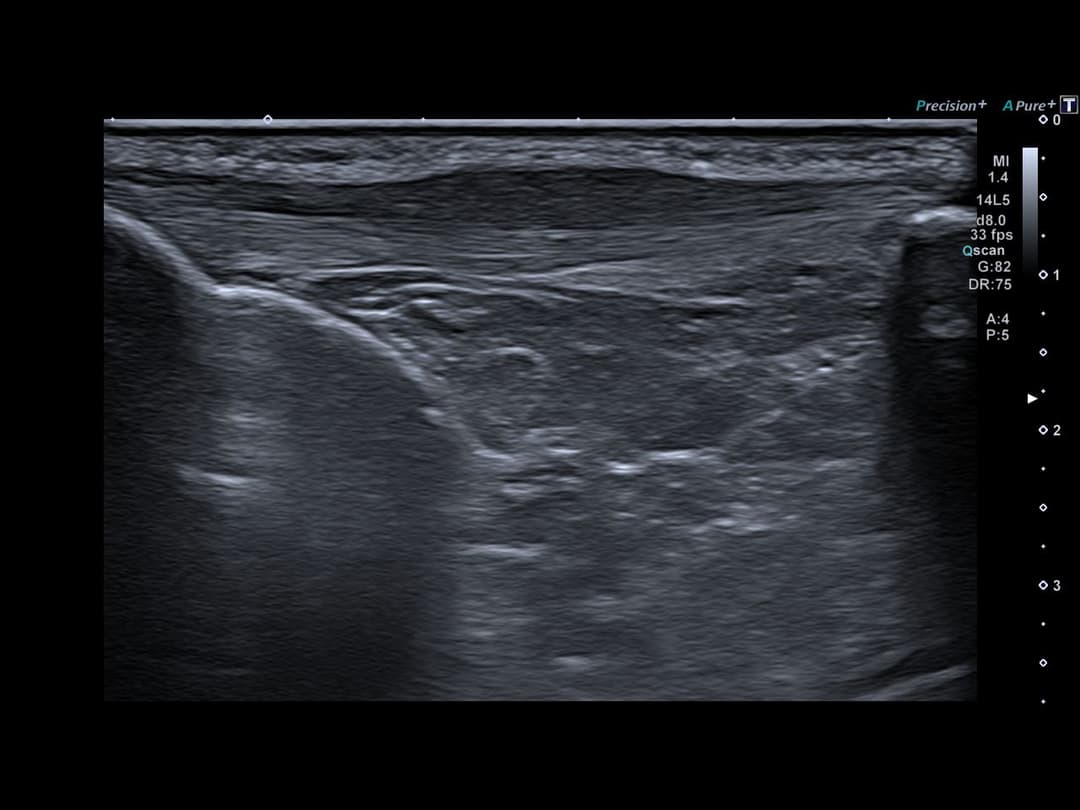

Tendinopathie patellaire corporéale superficielle

Échographie

Epaississement fusiforme avec hypo échogénicité de la portion corporéale superficielle du tendon patellaire, étendue sur 3cm de hauteur, sans fissuration intra-tendineuse notable.

Discret œdème des tissus mous cellulo-graisseux sous-cutanés adjacents.